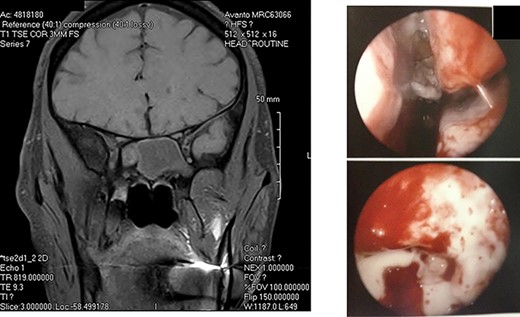

A: Magnetic resonance imaging (coronal view) reveals an expansile sphenoid sinus mass with fluid characteristics with extension into the cavernous sinus on the right. B: Intra-operative view through an endoscope reveals mucopurulent material from right sphenoid ostium. Sphenoid sinus reveals clumps of extramucosal ‘peanut buttery’ visco-elastic material (allergic mucin).

He was taken to the operating room, and an endoscopic exploration of sphenoid sinus was performed through sphenoethmoid recess. There was mucopurulent material drained through sphenoid ostium, and clumps of extramucosal ‘peanut buttery’ visco-elastic material (allergic mucin) were found in sphenoid sinus intra-operatively (Fig. 2B). One month post-operatively, patient’s visual acuity was 20/20, and extraocular movements revealed a minimal right abduction deficit.